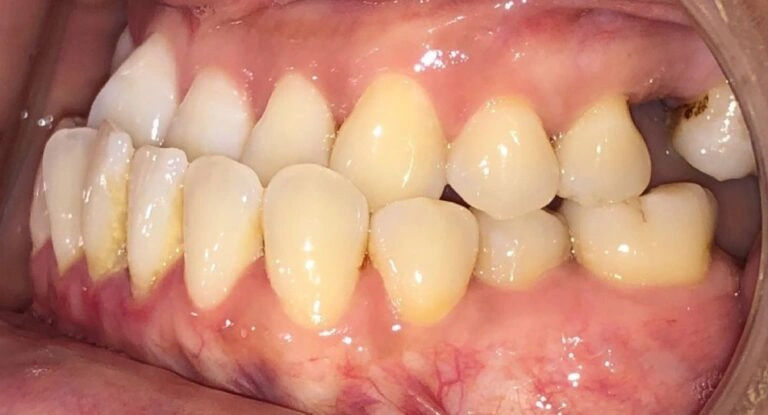

Visual Example:

Example #1 (young adult):

Example #2 (young adult):